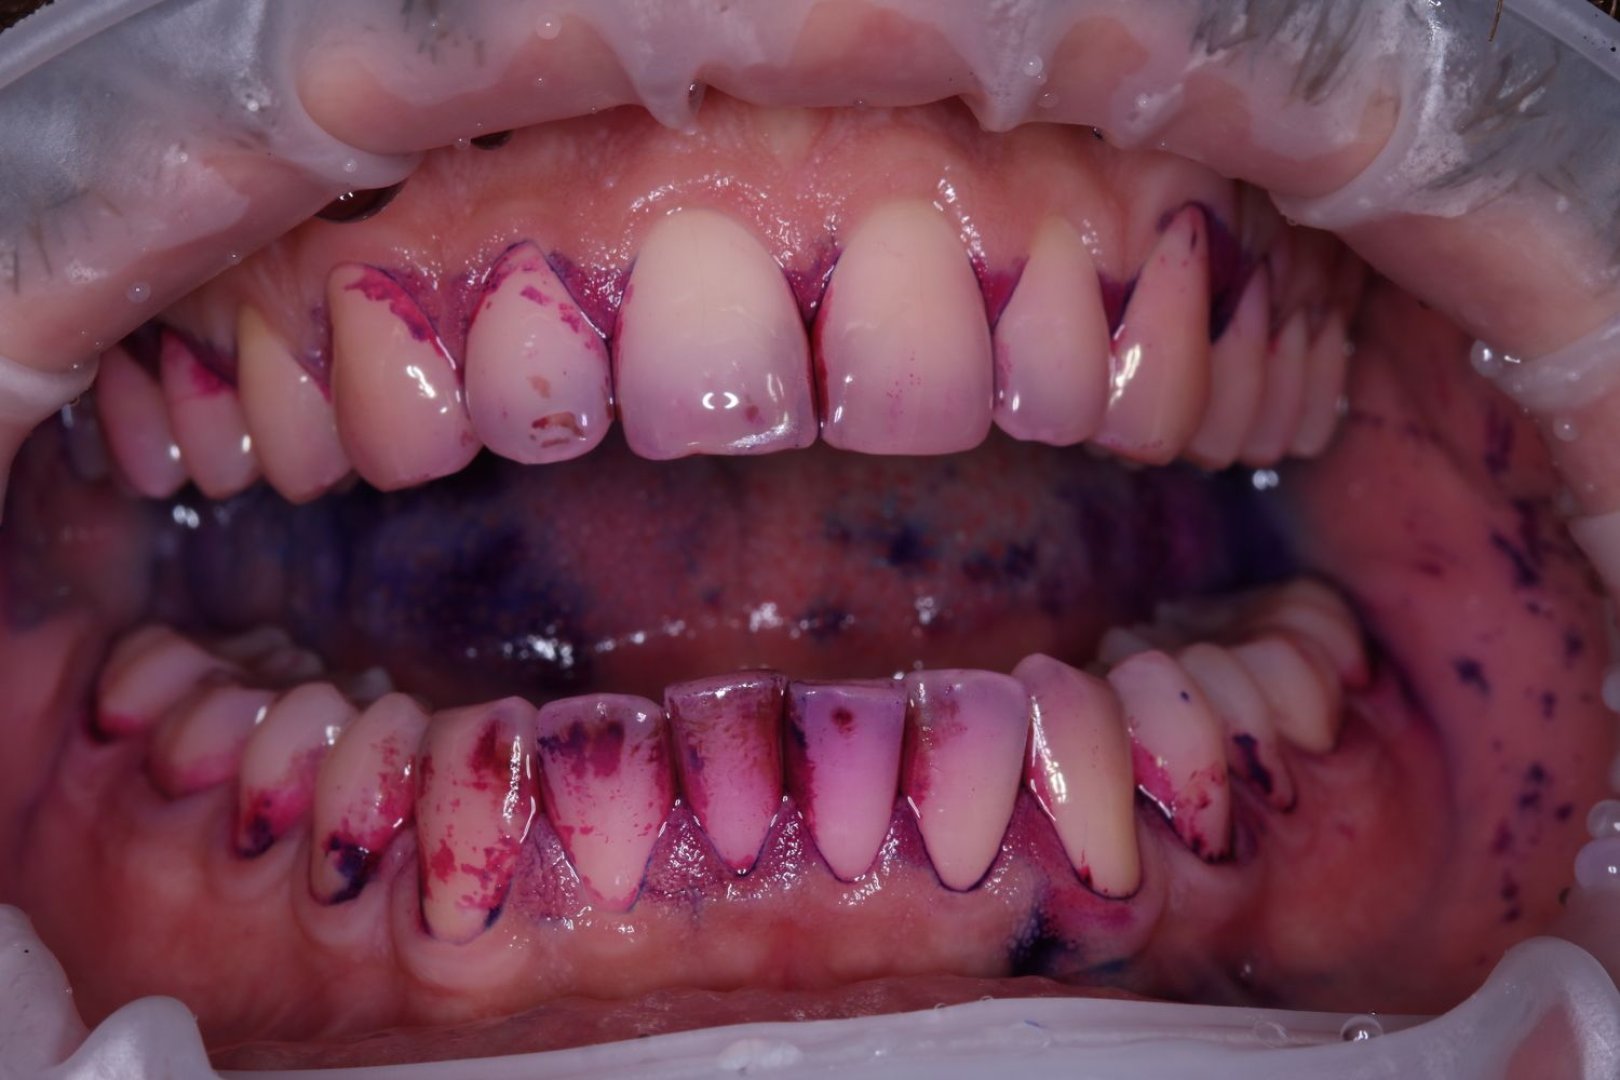

Профессиональная гигиена GBT

Проведение процедуры по протоколу Guided Biofilm Therapy с использованием технологии Airflow для бережного удаления пигментированного налета и последующим ультразвуковым снятием твердых отложений.

Дополнительные фото

udalenie-naleta-ot-kureniya-gbt-rabota-1

udalenie-naleta-ot-kureniya-gbt-rabota-2